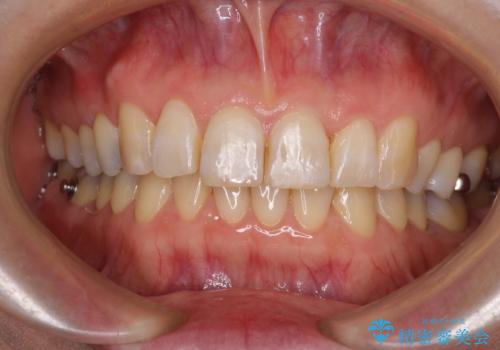

前歯のデコボコとむし歯だらけの歯列 矯正治療と虫歯治療

- むし歯が多く、歯並びも悪いとのことで、以前通院されていたご家族の紹介で来院された患者様です。

口腔内に無頓着であったため、まずはしっかりと歯磨きトレーニングを行い、必要な虫歯治療を行いました。

矯正治療は、むし歯が酷く抜歯が望ましい歯を1本抜歯して、ワイヤー装置にて整えることとしました。

矯正治療後は上顎前歯4本をオールセラミッククラウンにて補綴治療を行うこととしました。

むし歯が多かったため、ワイヤー矯正中に処置したむし歯が悪化することが懸念されましたが、歯磨きをしっかりと行ってくれたため、とても良好な状態を維持することができました。